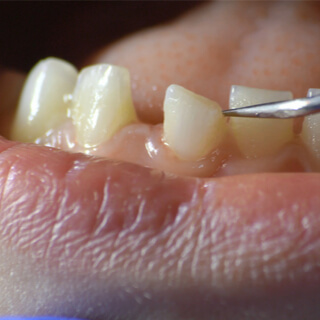

4. حركة الأسنان

تعد حركة الأسنان غير المبررة من اعراض سرطان الفك، وتعد من أكثر أنواع سرطان الفك الخبيث شيوعًا، وقد تلاحظ أيضًا أن أسنانك تتخلل أو أضبحت فضفاضة أو تتحرّك عن لمسها وقد تغيّر مكانها فجأة دون الشعور بذلك، وقد يتسبب الورم أيضًا في دفع الأسنان لتخرج من مكانها.